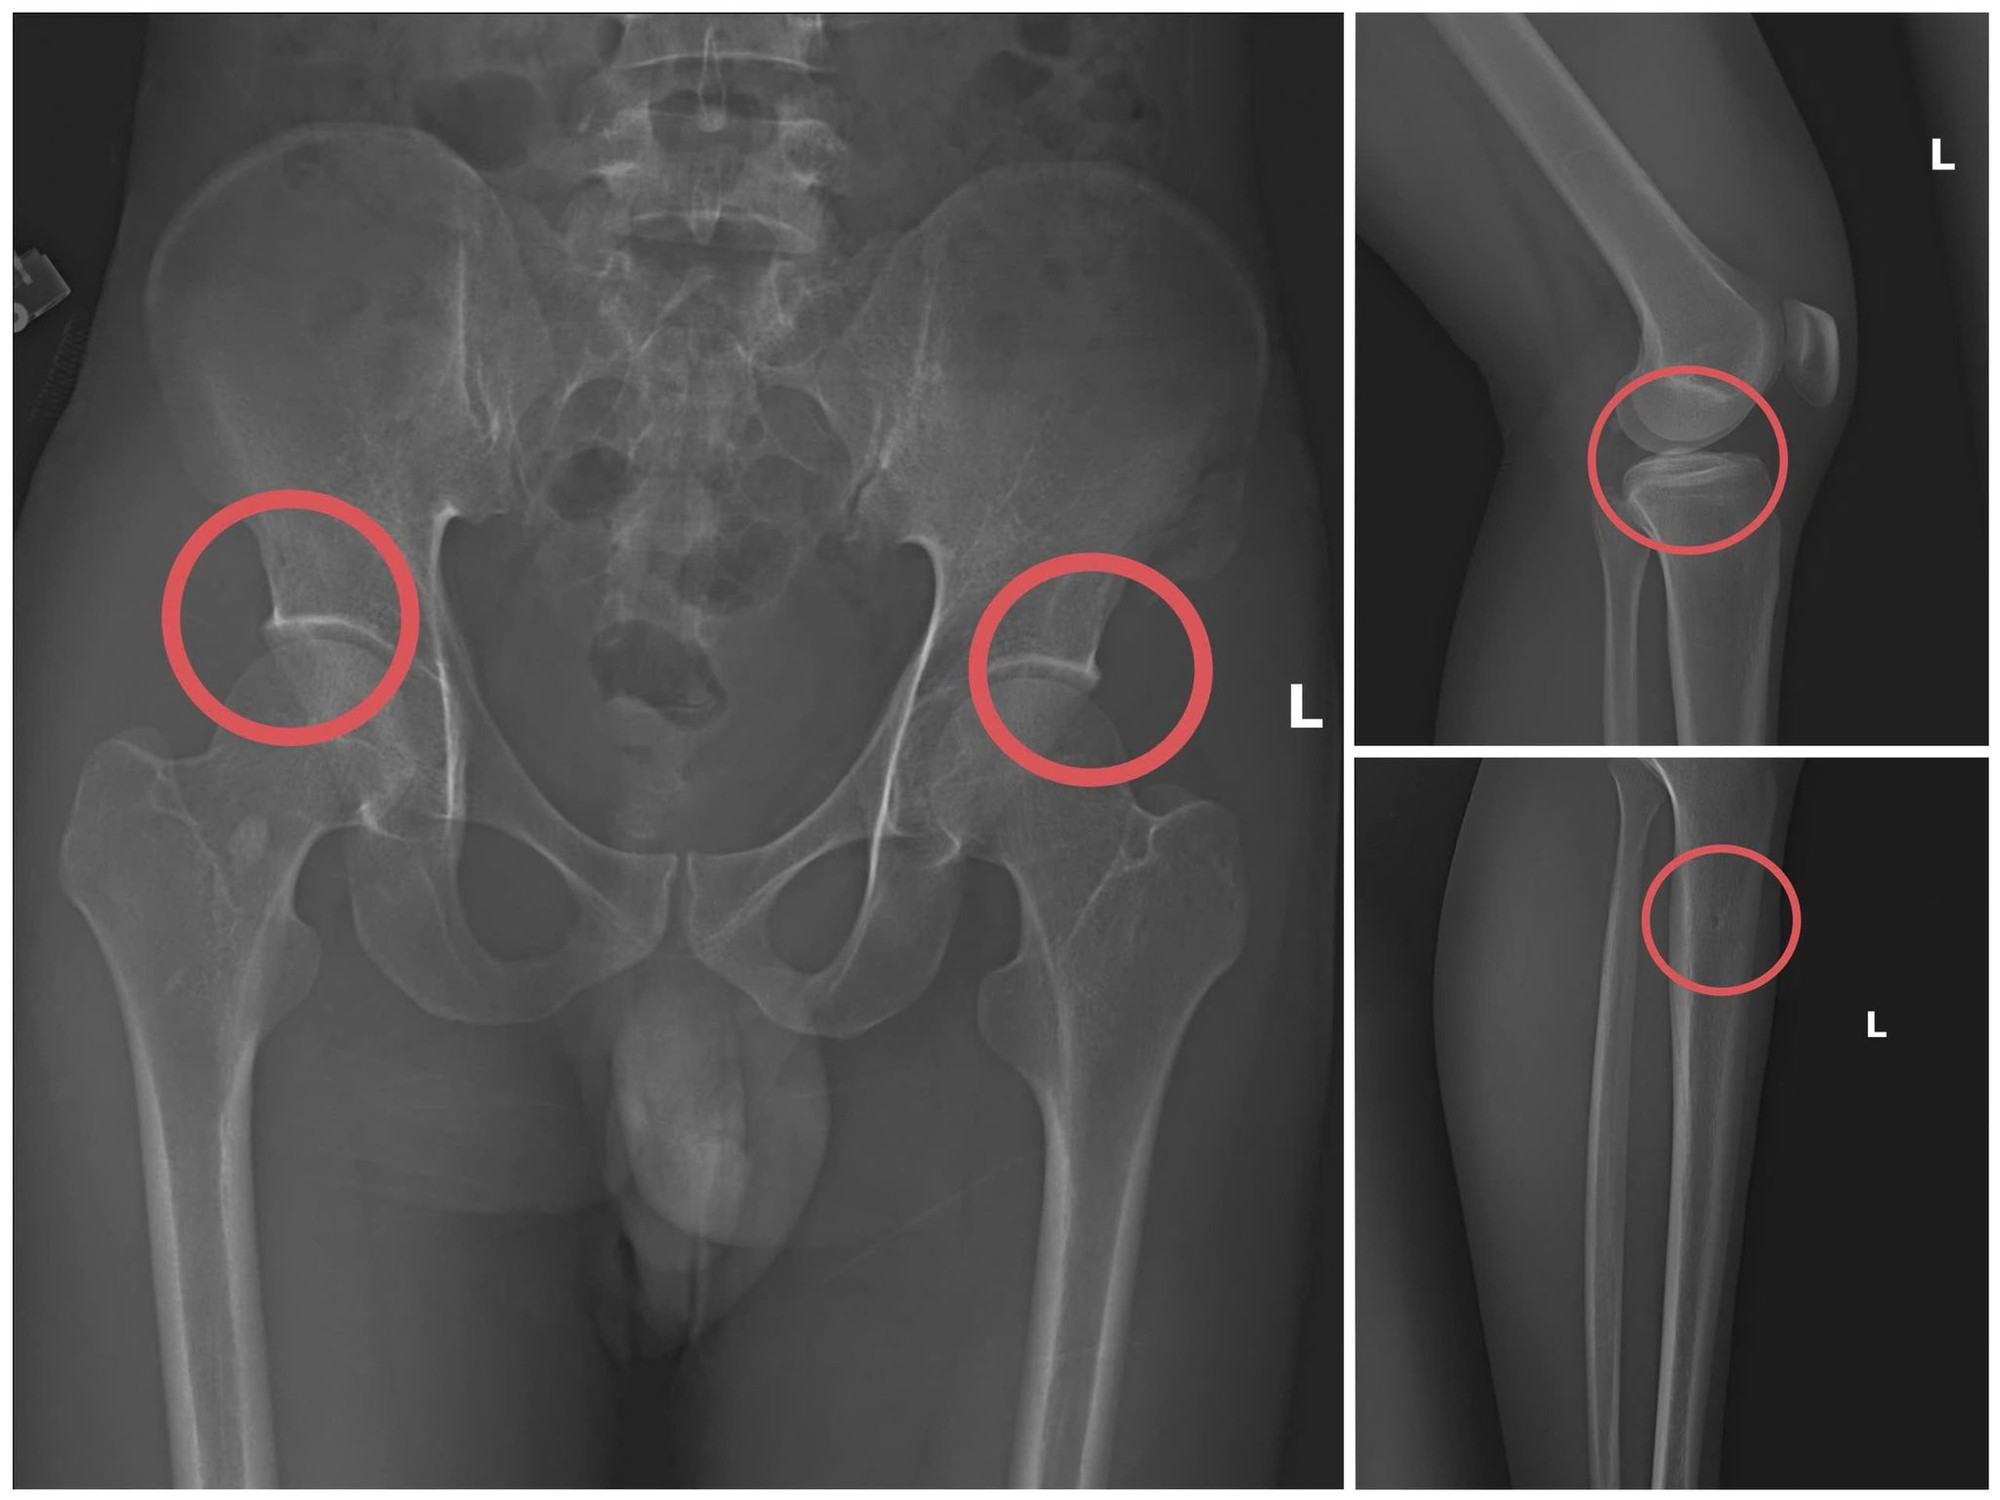

Tạ Minh Châu trực tiếp thực hiện hành vi tiêm thuốc mê, dùng búa đinh tác động vào xương người mua bảo hiểm, tạo nên các vết nứt xương tương tự tai nạn thật. Khi thương tích đã tạo xong, Châu tiếp tục hướng dẫn các đối tượng dựng hiện trường giả như điện giật ngã, trượt chân ngã suối nhằm hợp thức hóa bệnh án và hoàn thiện hồ sơ yêu cầu chi trả.

Các đối tượng dùng búa đập vào xương tạo ra thương tích để chiếm đoạt tiền của các công ty bảo hiểm. Ảnh: Công an cung cấp

Theo cơ quan công an, đây là thủ đoạn vô nhân tính, coi thường sức khỏe, tính mạng của người tham gia. Đối tượng đã tính toán kỹ để gây thương tích đúng vị trí có mức chi trả cao, khiến các công ty bảo hiểm khó phát hiện dấu hiệu gian dối.